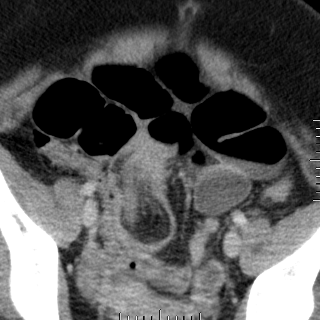

| Aspect radiologique ASP

de occlusion intestinal : Image hydro-arerique

des anses de l' intestin dilate et isolee au milieu de

l'abdomen . Les plies muqueuse de l'intestin sont

multiple et image de vide en aval de l'obstacle (

n'as pas image de air dans la region pelvienne ) |

Image en escalier typique de

occlusion de l'intestin grele . L'intestin est tres

dilate depasse 36mm de diametre et les niveaux hydrique se situe en

escalier

au milieu de l'abdomen . |